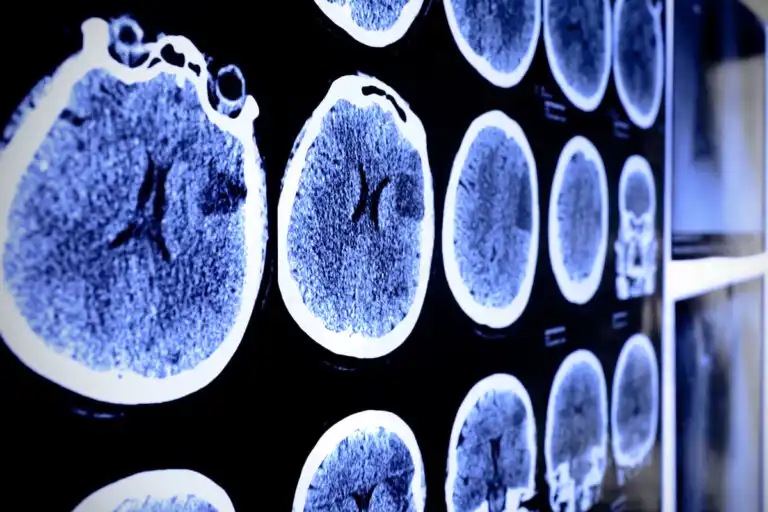

تعد دراسة التصوير أمرًا حيويًا لتحديد أمراض الورم على مستوى أنسجة المخ. بشكل عام ، التصوير بالرنين المغناطيسي (MRI) هو الأكثر استخدامًا في تشخيص الورم النجمي.

وعادة ما يتم إجراؤه مصحوبًا بوسائط تباين تسهل تحديد مكان الورم ووضع خطة علاجية.

- التصوير المقطعي (CT).

تعتبر الخزعة بالإبرة جزءًا مهمًا من التشخيص النهائي لورم الدماغ. يمكن إجراؤه مسترشدًا بالتصوير بالرنين المغناطيسي أو التصوير المقطعي المحوسب . يجب إرسال العينة التي تم الحصول عليها إلى أخصائي علم الأمراض.

تسمح الدراسات المجهرية بترتيب أو تصنيف ورم الخلايا النجمية من أجل تحديد التشخيص وتحديد السلوك العلاجي مع المريض.